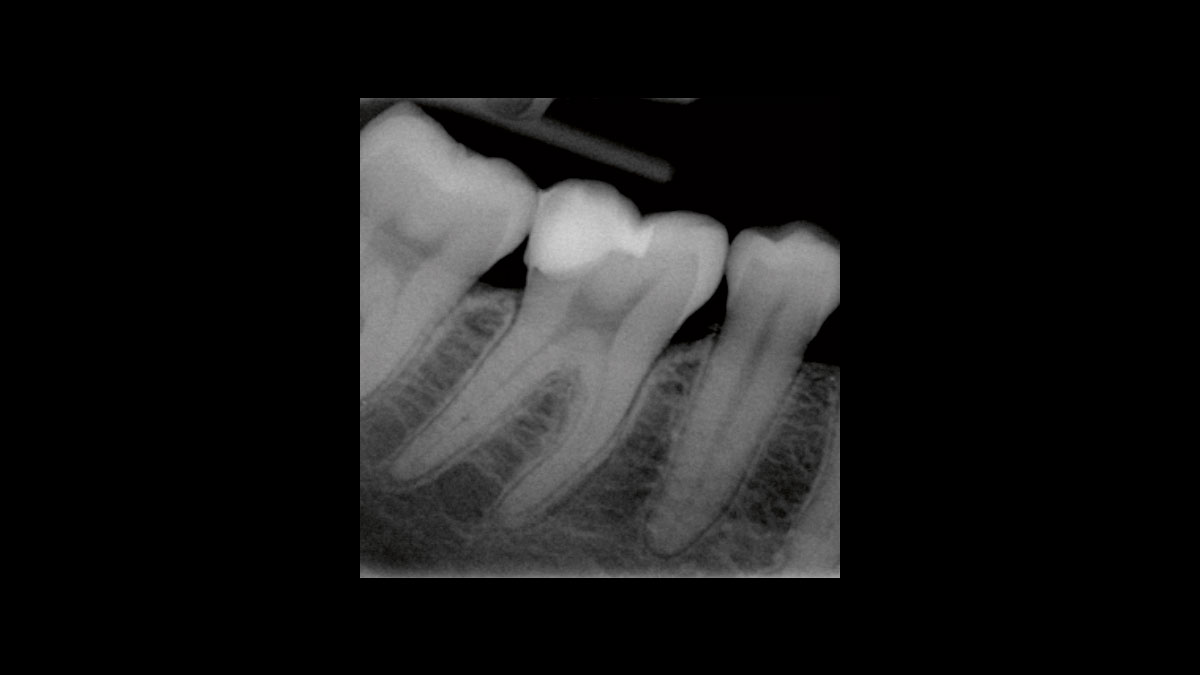

Periodontology

The following applications are presented in the videos and images:

• Periodontic germ reduction

Periodontic germ reduction